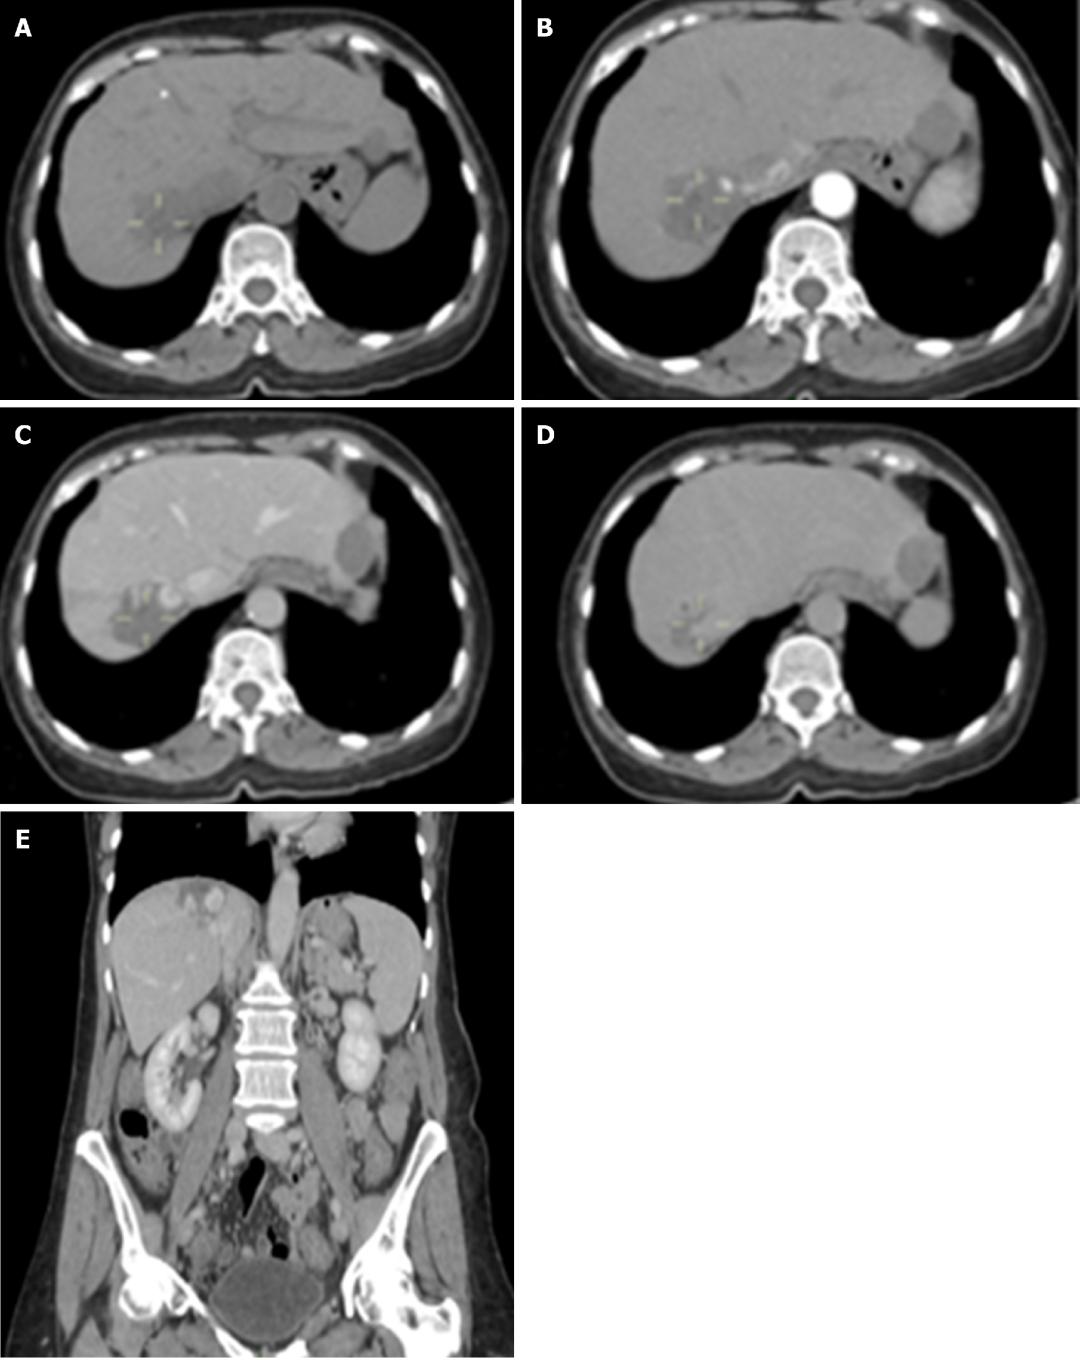

诊断 :HH的诊断目前主要依赖于影像学检查,多种检查手段联合应用可提高诊断准确率。常规首选超声检查,再结合CT、MRI以及数字减影血管造影检查等综合判断。

图2 CT检查